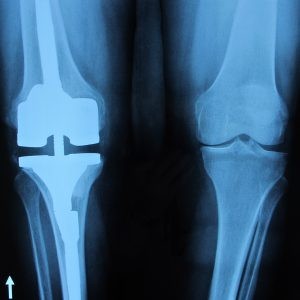

Φωτογραφία 3η: Ακτινογραφία γόνατος με ολική αρθροπλαστική γόνατος

Κατά την επέμβαση της ολικής αρθροπλαστικής, η αντικατάσταση της επιγονατίδας ή όχι είναι ένα αντικρουόμενο ζήτημα μεταξύ των ορθοπεδικών. Έτσι υπάρχουν δύο σχολές, η, κυρίως Αμερικάνικη, σχολή κατά την οποία η επιγονατίδα αντικαθίσταται με μία πλαστική κατά την διάρκεια του χειρουργείου και η, περισσότερο Ευρωπαϊκή, σχολή κατά την οποία η επιγονατίδα μένει ανέπαφη και γίνεται νεαροποίηση της.

Πάντα σε τέτοιες περιπτώσεις διχογνωμιών δεν υπάρχει χρυσός κανόνας αλλά υπάρχουν πλεονεκτήματα και μειονεκτήματα και στις δύο περιπτώσεις.

Εμείς σε γενικές γραμμές προτιμάμε την ολική αρθροπλαστική του γόνατος με την χρήση τσιμέντου. Επίσης, την αντικατάσταση του οπίσθιου χιαστού συνδέσμου, χωρίς αντικατάσταση της επιγονατίδας. Όμως η επιλογή μας προσαρμόζεται στις ανάγκες του ασθενούς που προκύπτουν από τη ηλικία του, τις δραστηριότητες του κλπ.